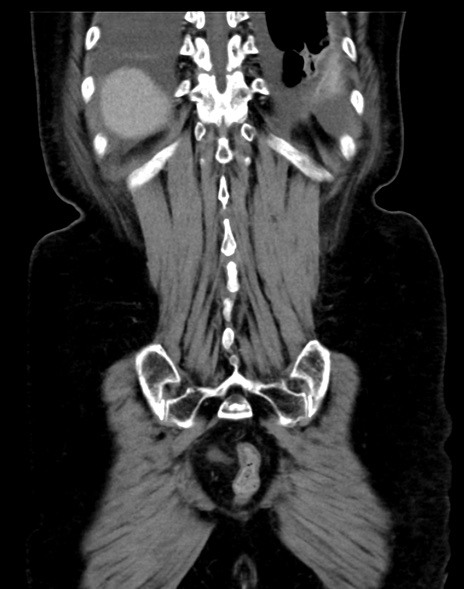

症例13 CT(冠状断像)1日半後